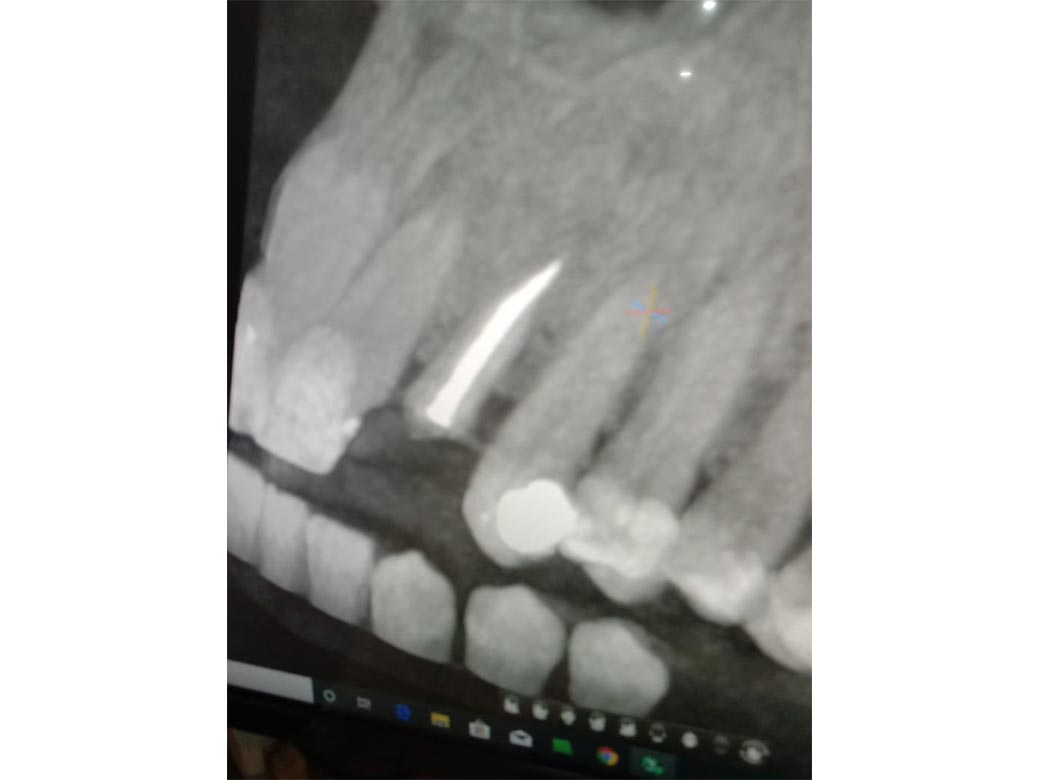

Step : CBCT was taken in our centre. Reports showed only root piece left inside the tooth socket. So, treatment was planned. In her case scenario the plan was to remove the left out root piece followed by implant placement & immediate capping.

Step 1 : X-ray taken.